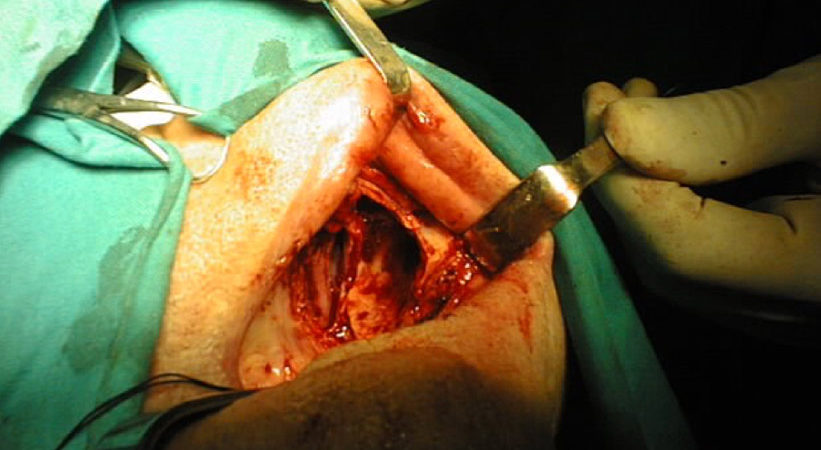

Donna di 82 anni portatrice di un carcinoma squamoso multifocale del cavo orale infiltrante la mandibla T4N0.

Una mandibulectomia marginale è stata effettuata con tecnica piezoelettrica.